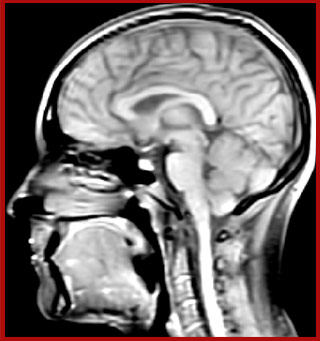

The techniques for measuring myelin have changed a lot over the years. “Since we are using the Elition, our myelin water images are much better. We're now acquiring 1 x 2 x 5 mm voxels and displaying at 1 x 1 x 2.5 mm. For a whole brain we can now measure the fraction of water in the myelin component in only about five or six minutes,” Dr. MacKay says.

of limiting MWI to the brain, even without the cerebellum, we can now spend about the same amount of time and scan the whole brain and the cervical spinal cord, which is a huge boost for us.” Dr. Rauscher says, “For MWI we perform 3D T2 with 32 or more echoes. This used to take a long time, but with Compressed SENSE we can decrease this to ten minutes for the whole head. Because of the large field of view (FOV) on the readout direction, we even get information from the brainstem, which we previously missed when we were using the GRASE approach. Having the whole head scan is nice because it has spatial resolution, orientation and FOV that are comparable to the standard 3D clinical MS scans, including the FLAIR and 3D T2, and a 3D T1 for brain volume.”

T1 - weighted

Myelin water imaging (echo 1)

With SENSE

With Compressed SENSE

Acquired resolution:

1 x 2 x 5 mm3

→

1.5 x 2 x 3 mm3

Number of echoes:

32 or 48

56

Echo spacing:

10 ms or 8 ms

7 ms

T1 - Weighted, Myelin Water Fraction Superimposed

Spinal cord coverage

Smaller, more isotropic voxels

Excellent detail in quantitative maps

Images courtesy of Adam Dvorak, Department of Physics and Astronomy, University of British Columbia

According to Dr. MacKay, MWI images benefit from Elition’s high quality gradients. “We need good gradients because we want to be able to do multi-echo sequences that have short TE times.”

Dr. Rauscher says, “With better gradients we can use a shorter echo spacing on the spin echo, so we get better sampling of the rapidly decaying myelin signal, which typically has T2 of around 10-20 milliseconds at 3 Tesla. If we can reduce echo spacing from about 8 to 5-6 milliseconds, we get a much better sampling of the short decay component and increase our SNR, which is a big advantage. The same is true for multi-echo gradient echo which we use for susceptibility mapping and for mapping venous vessels in MS.”